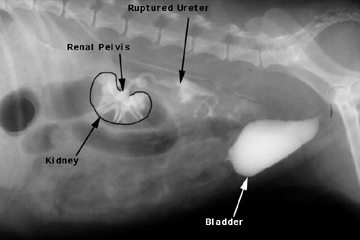

A lateral view of an IVP. Notice the contrast medium leaking from the ruptured ureter.